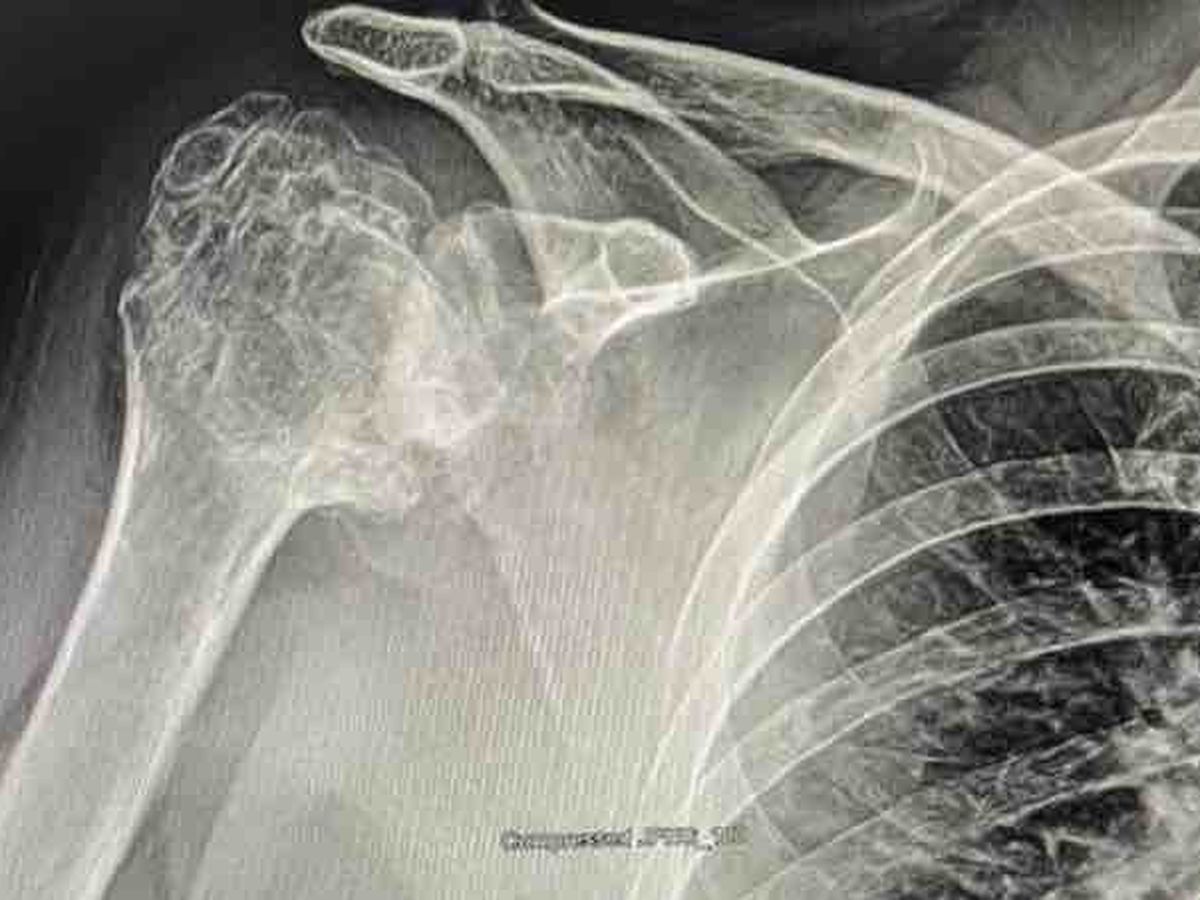

Hi everyone, I’m fundraising to help my mom to get a new humerus, she needs as soon as possible to replace her damaged humerus for a prosthesis one.

Hola a todos, estoy recaudando fondos para ayudar a mi mamá a obtener un nuevo húmero, ella necesita lo antes posible reemplazar su húmero dañado por una prótesis.